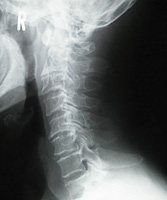

3.変形性頚椎症・頚椎症性神経根症

椎間板の退後変性に基づき、椎間板腔の狭小化・椎体辺縁の骨棘形成・椎間関節の狭小化により、首の動きを悪くしたり、痛みを誘発します。

頸椎の変化は主に加齢や外傷が原因で起こります。加齢による頸椎の変化には個人差がありますが、一般的には40歳ごろから明らかになります。

高齢になるほどその変化が強くなるため、頸椎症は中高年者で多く発症します。